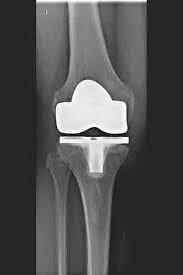

KNEE REPLACEMENT (ARTIFICIAL KNEE JOINT)

The artificial knee joint replaces the cartilage surface destroyed by arthrosis. The underlying bone on the thigh and tibial head remains intact. Some people compare a modern artificial knee joint to a crown on a tooth; the exact term is the so-called bicondylar surface replacement. Between the new surfaces on the thigh and lower leg is the so-called inlay made of a specially hardened white plastic, which can be seen in the X-ray image as the gap between the metal parts.